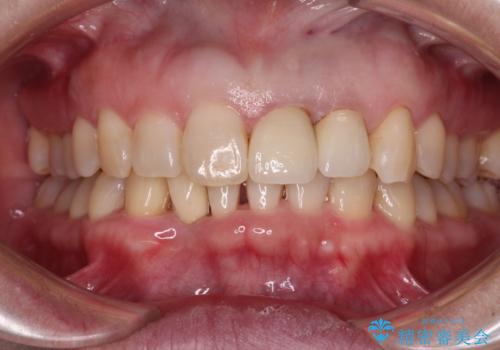

- 下顎前歯が抜けそうとのことで来院された患者様です。

初診の状態ではすぐにでも抜けそうな状態で、インプラントによる補綴治療を行うこととしました。

インプラント治療に際し、前歯の叢生に対する矯正治療を提案したところ、興味を持たれたので、インビザライン・ライトによる矯正治療を行うこととしました。

抜歯後にスペースができると恥ずかしいため、抜歯した歯を接着剤で固定した上で矯正治療を行い、その後インプラントやオールセラミッククラウンの装着を行うこととしました。